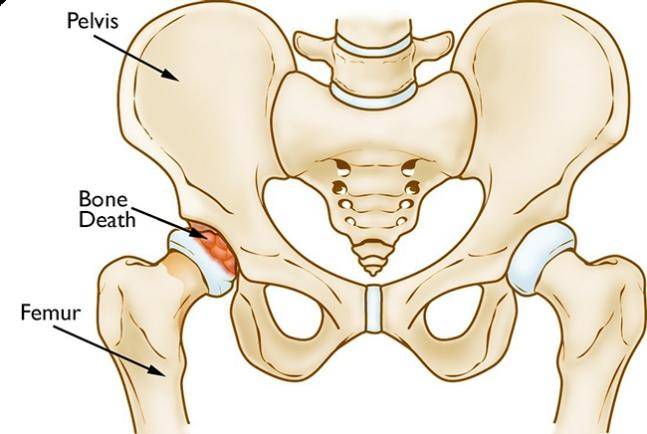

股骨头坏死

图片尺寸3968x2976